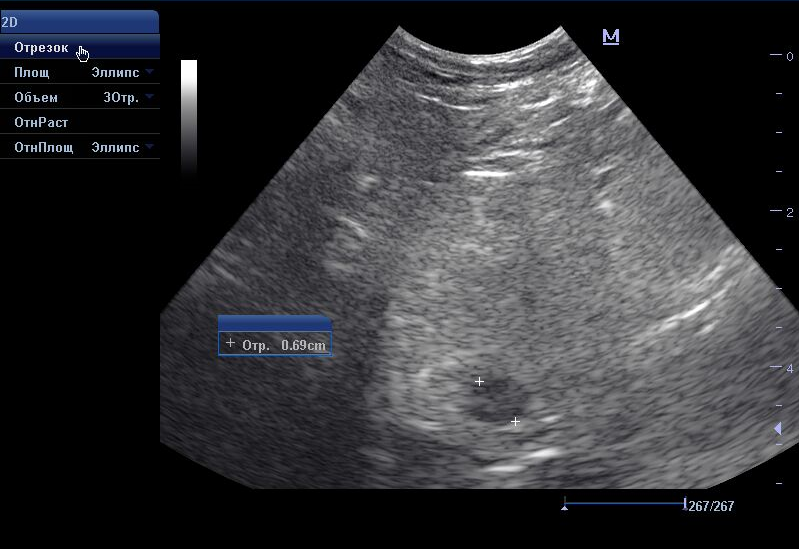

В норме при УЗИ предстательная железа с четким ровным контуром, однородная, зернистая, без патологических образований. Простатическая часть уретры не расширена. Доли симметричные, округлые. Нормальные размеры предстательной железы у кобелей 2-4см.